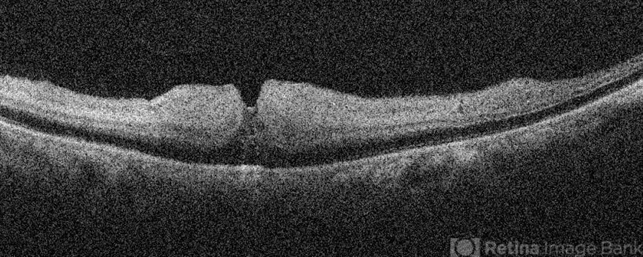

- Left eye OCT of a 75 year old male with central retinal artery occlusion showing altered foveal contour with loss of differentiation of layers with thickening.